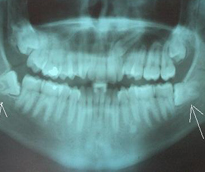

Oral Diagnoz ve Radyoloji